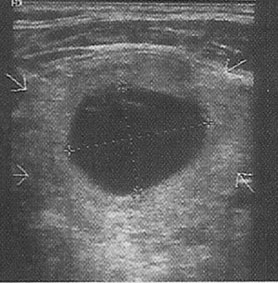

Ultrasonda nodülün içi tamamen sıvı ile dolu ise kistik nodül (şekil 1), tiroit kaynaklı doku ile dolu ise katı nodül (solit nodül) (şekil 2), hem doku hemde sıvı içeriyorsa karışık nodül (mikst nodül) (şekil 3) adını alır.

Şekil 1: Kistik nodül ![]() | Şekil 2: Katı nodül ![]() | Şekil 3: Karışık nodül ![]() |